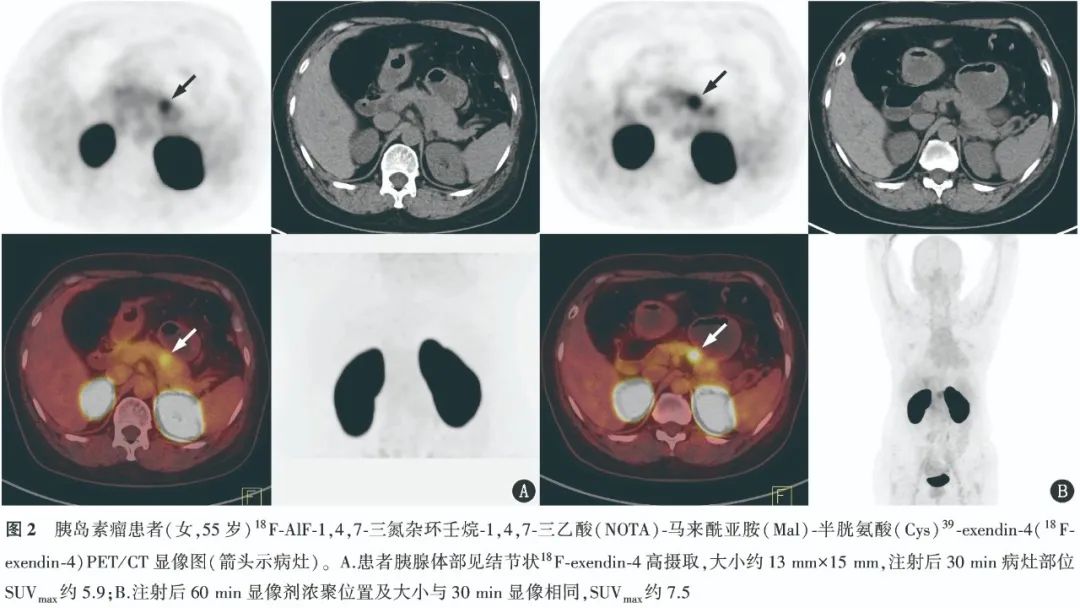

3. 18F-exendin-4 PET/CT顯像。 患者注射前、注射后20 min以及注射后50 min的指尖血糖分別為4.94、4.43和4.02 mmol/L。注射后30 min行PET/CT腹盆部顯像,結果顯示胰腺體部見結節(jié)狀18F-exendin-4高攝取,大小約13 mm×15 mm,SUVmax約5.9。注射后60 min的全身顯像結果顯示,18F-exendin-4高攝取病灶的位置及大小與30 min顯像相同,SUVmax約7.5。PET/CT顯像圖如圖2所示。查詢醫(yī)院病例系統(tǒng)中該患者的術后病理結果,顯示胰腺包塊為腫瘤性病變;腫瘤細胞免疫組織化學結果顯示,人角蛋白抗原決定簇5.5(+)、CD10(+)、CD56(+)、CD99(+)、嗜鉻粒蛋白A(+)、細胞角蛋白(核旁點狀+)、G1/S-特異性周期蛋白D1(部分+)、上皮膜抗原(-)、胰島素瘤相關蛋白1(+)、細胞增殖核抗原Ki-67(約4%+)、孕激素受體(+)、突觸素(+)、波形蛋白(-)、β-連環(huán)蛋白(包膜+、胞質(zhì)+),符合NEN(G2)特征。

5. 18F-exendin-4 PET/CT 顯像。 患者女,55歲,5年前出現(xiàn)晨起后低血糖發(fā)作伴意識障礙,持續(xù)約10 min,排除癲癇相關疾病。CT、超聲等未見明顯異常,MRI結果顯示,胰腺體部見一稍長T1稍長T2信號結節(jié)影,長徑約15 mm,考慮胰島素瘤。患者晨起進食后于本科簽署知情同意書并行18F-exendin-4 PET/CT顯像。顯像時,患者全程持續(xù)滴注質(zhì)量分數(shù)10%葡萄糖注射液,并分別于注射前、注射后20 min以及注射后50 min監(jiān)測指尖血糖。按體質(zhì)量4.44 MBq/kg的劑量進行18F-exendin-4靜脈注射后,患者平躺休息,于注射后30 min及60 min進行圖像采集,采集范圍分別為腹盆部及全身(至股骨下緣)。使用Flow模式進行全身采集。CT采集參數(shù):管電壓120 kV,管電流自動mA,層厚3.0 mm,層間距2.0 mm,螺距0.8 mm。圖像重建方法為TrueX+飛行時間,經(jīng)計算機2次迭代、每次迭代21個子集重建,矩陣大小256×256。通過德國Siemens syngo VH210,TrueD工作站進行圖像融合和SUVmax測定。該項目經(jīng)四川省醫(yī)學科學院·四川省人民醫(yī)院倫理委員會審查并批準(批準號:2023年第375號)。